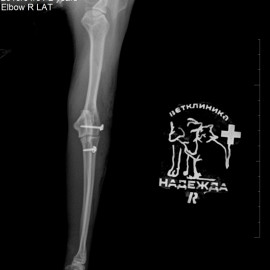

Кот Тимоша. Жалобы на хромоту на правую переднюю лапу в течение нескольких дней. После осмотра и рентгенографии был поставлен диагноз: вывих правого локтевого сустава. Была проведена операция: остеосинтез правого локтевого сустава.

Снимки 2-3 после операции